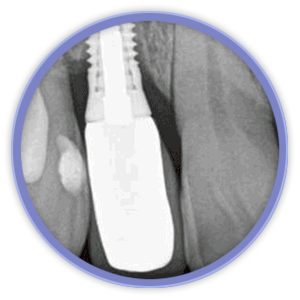

El aspecto más revolucionario en este ámbito fue la aparición de los implantes dentales que son unos pequeños bloques de titanio, con forma de raíz dental, que se insertan dentro del hueso mandibular o maxilar del paciente y sirven de sujeción para dentaduras, puentes o coronas, mejorando así la calidad de vida y aumentando las posibilidades de tratamiento de los pacientes.

La magnificación de la imagen mediante lupas o microscopio dental nos permiten niveles de acabado y de precisión mucho más exigentes. Actualmente la importancia de la estética gingival (encías), ha obligado a desarrollar técnicas de regeneración de hueso y tejidos blandos, que complementan a las cirugías de implantes entre otras.